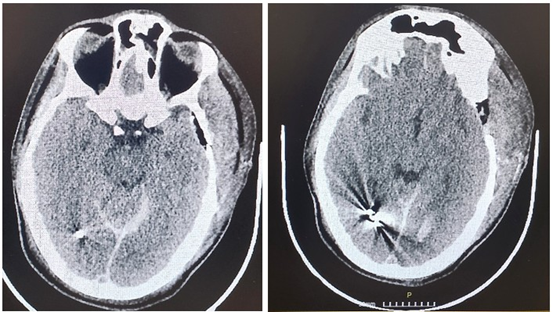

During the neurosurgical procedure, the following stages were performed: Left craniectomy, meningeal section and opening. A small puncture of the anterior part of the sagittal is found where the bleeding is successfully stopped. Wound closure in layers. He was taken under full sedation to the Intensive Care Unit (Figures 1-4, a and b).

Figure 2(a and b): CT Brain scan 5 days after the brain injury and the neurosurgery.